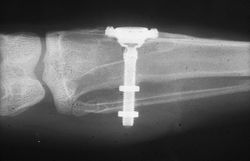

Radiograph of Brånemark's initial rabbit specimen, showing the titanium optic chamber fixed to the rabbit's tibia and fibula. The distal extent of the rabbit's femur can be seen at the left of the radiograph, completely unrelated to the screw, despite some sources (such as Block & Kent's textbook) claiming that Brånemark's study involved the femur.